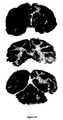

FIG. 39. Brain scans of adult Rhesus monkey at 3 hours after the intravenous administration of the [125I]-fusion antibody demonstrates widespread distribution of the fusion antibody into the primate brain in vivo from blood. The top scan is the most frontal part of brain, and the bottom scan is the most caudal part of brain, and includes the cerebellum.